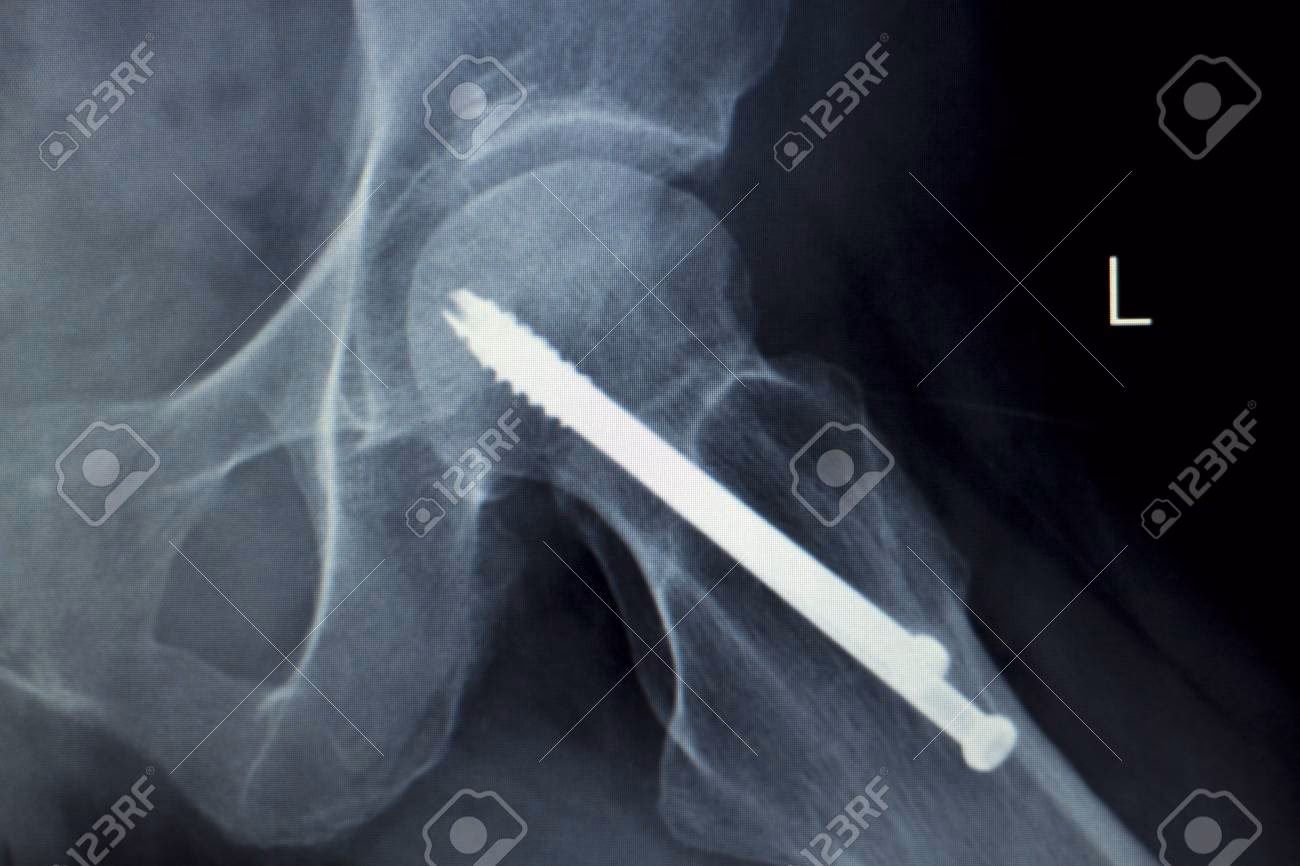

- Placas Óseas para Reparación de Fracturas: Utilizadas ampliamente para tratar fracturas mediante reducción anatómica, estas placas, junto con tornillos, alambres y clavos, mantienen unidos los fragmentos óseos. Su objetivo es restaurar las funciones del tejido óseo, permitiendo la curación y la recuperación del movimiento. Los metales como el acero inoxidable, las aleaciones de Co-Cr o el titanio son los materiales de elección por su resistencia y durabilidad.